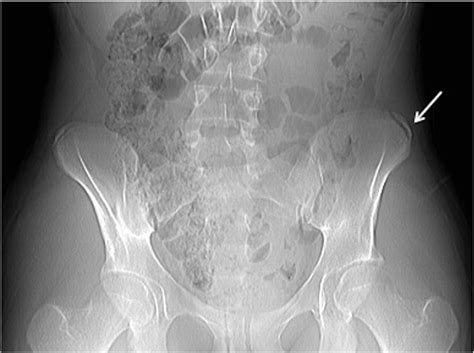

Anteroposterior and oblique radiography of the pelvis is done in patients who have acute onset of pain to determine the presence of an avulsion fracture 6. Avulsion fracture of the iliac crest is an uncommon pathology.

This can occur at the ligament by the application of forces external to the body (such as a fall or pull). A pelvic avulsion fracture occurs when the tendon of a muscle comes away from the bone, taking a small chip of bone with it. This most commonly occurs at bottom of the ischium where the big hamstring muscles are attached, or on the front of the ilium where. The area of the left iliac crest was painful and active mobilization of the left hip was totally impossible. The iliac crest may develop fracture due to hip trauma or complications in bone marrow donors. Avulsion fractures of the apophysis of the iliac crest have rare incidence and are little known. This can occur at the ligament by the application of forces external to the body (such as a fall or pull). A patient with iliac crest pain usually feels pain throughout the lower back, core. Pain occurring in iliac crest may be an indication of an inflammation within the iliolumbar ligament. What causes pelvic avulsion fractures? Learn how most avulsion fractures are treated. Iliac crest autograft contains all three properties for bone formation and remains the gold standard for fusion procedures as it has a number of advantages. Hence, autologous bone grafts are gathered from the iliac bony crest in this reconstructive surgery and used to promote healing of bones in fractures or to lend physical support for the operation. However, those that occur at the iliac crest are rare. A rare fracture in adolescent athletes. Avulsion fracture of the lateral 1/4 of the right iliac crest apophysis. Avulsion fracture of the iliac crest following bone grafting is an extremely rare occurrence.